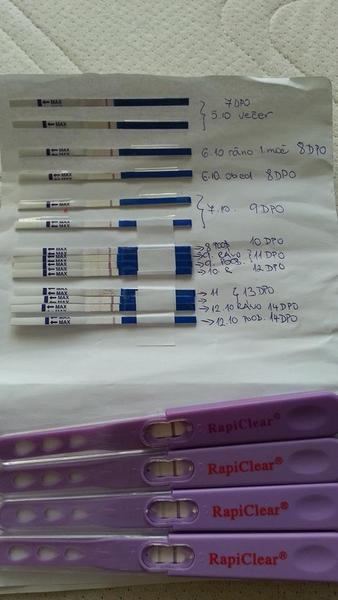

@nikola81 ja som mala presne tento isty problem.. poobede som mala // a rano som mala vzdy slabucky test alebo iba jednu ciarku.. jas om tetovala kazdy den bo som bola z toho na nervy.. 😀

@tinushka13 tolko testov som este v zivote pokope nevidela :DDDD ja by som si ich tiez chcela robit kazdy den, ale uz som sa zmiernila 🙂 ale gratulujem 🙂 nech vsetko dobre dopadne a o par mesiacov si stastna maminka 🙂))

@margotka23 ja by som si ich tolko nerobila.. len prvy test mi vysiel pozitivny 5DPO.. to som bola totalne v soku.. potom som skuila dalsi.. ten bol negativny.. potom opat pozitivny a takto sa to stale akosi menilo a ja som bola zufala ze ci vobec som alebo niecom.. dokonca aj digi mi povedal ze NIE.. a testy tmavli. 😀 takze ja som z cisteho zufalstva nevedomosti musela pre pokoj svojej dusicky 😀 teraz sa nad tym rehocem ako kobyla 😀 a dakujem pekne taktiez tak prajem 😀

@anickaan ja som testovala 5DPO 😀 ale myslim že som mala šťastie.. dva ukázali a potom neukázali a o pár dní opäť ukázali.. 😀